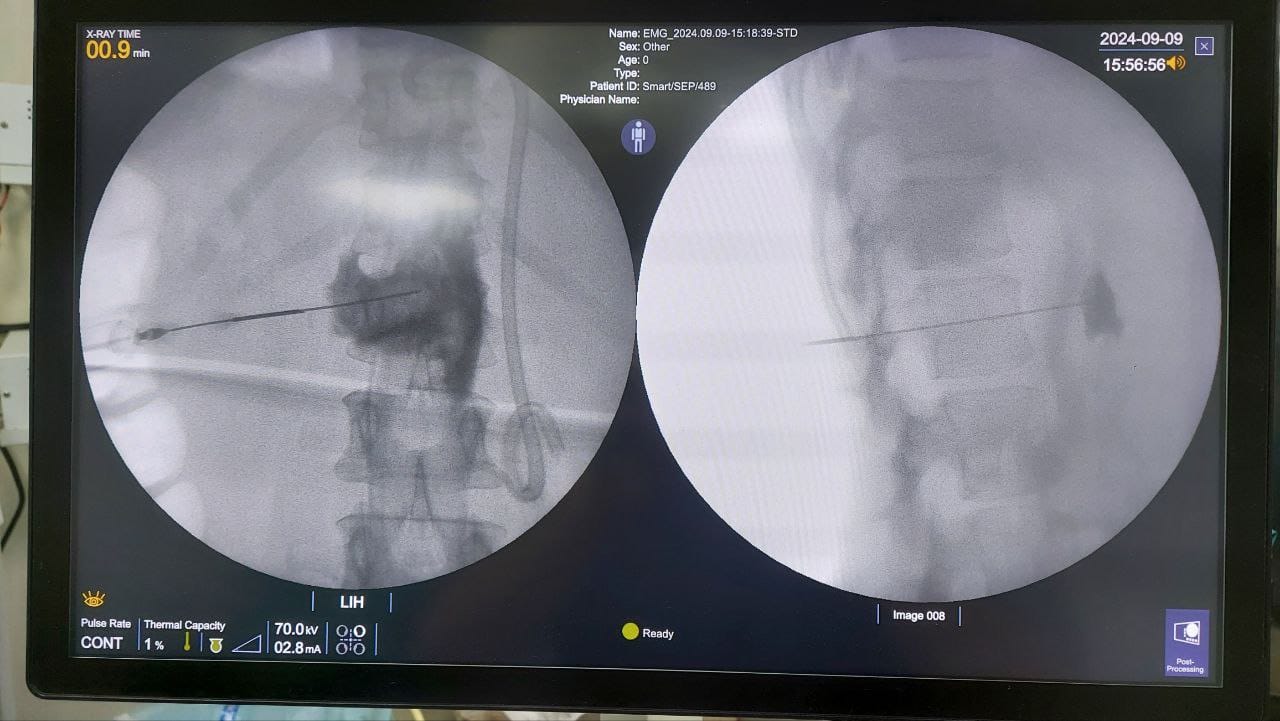

Procedures